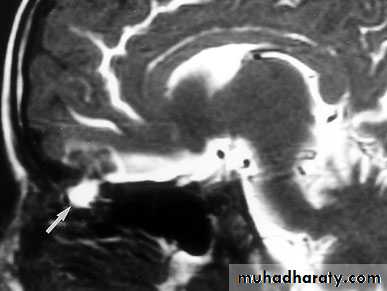

Cerebrospinal fluid (CSF) Rhinorrhoea

Aetiology

Trauma: fracture of the base of the skull e.g. the cribriform plate and the posterior wall of the frontal sinusSpontaneous: Destructive lesion involving the floor of the anterior cranial fossa

Clinical Picture

Watery fluid drips from the nose which increase in bending forward.

Meningitis.

Examination

Handkerchief test: The fluid associated with rhinitis contains mucous which stiffens a handkerchief while CSF does not.

Nasal endoscope to see the site of the lesion.

Investigations

Identification of glucose in the secretion.

Injection of radioactive material into CSF via lumber puncture.

CT. scan of the base of the skull.

Treatment

MedicalBed rest in head up position.

Systemic antibiotics.

Avoidance of nose blowing and avoidance of nasal packing.

Reduction of CSF production rate by drugs ( acetazolamide , frusemide ) or by repeated lumber puncture.

2- Surgical: if no response to medical treatment after 10-14 days, then;

Treat the cause.

Craniotomy and fascial graft of the leaking site.